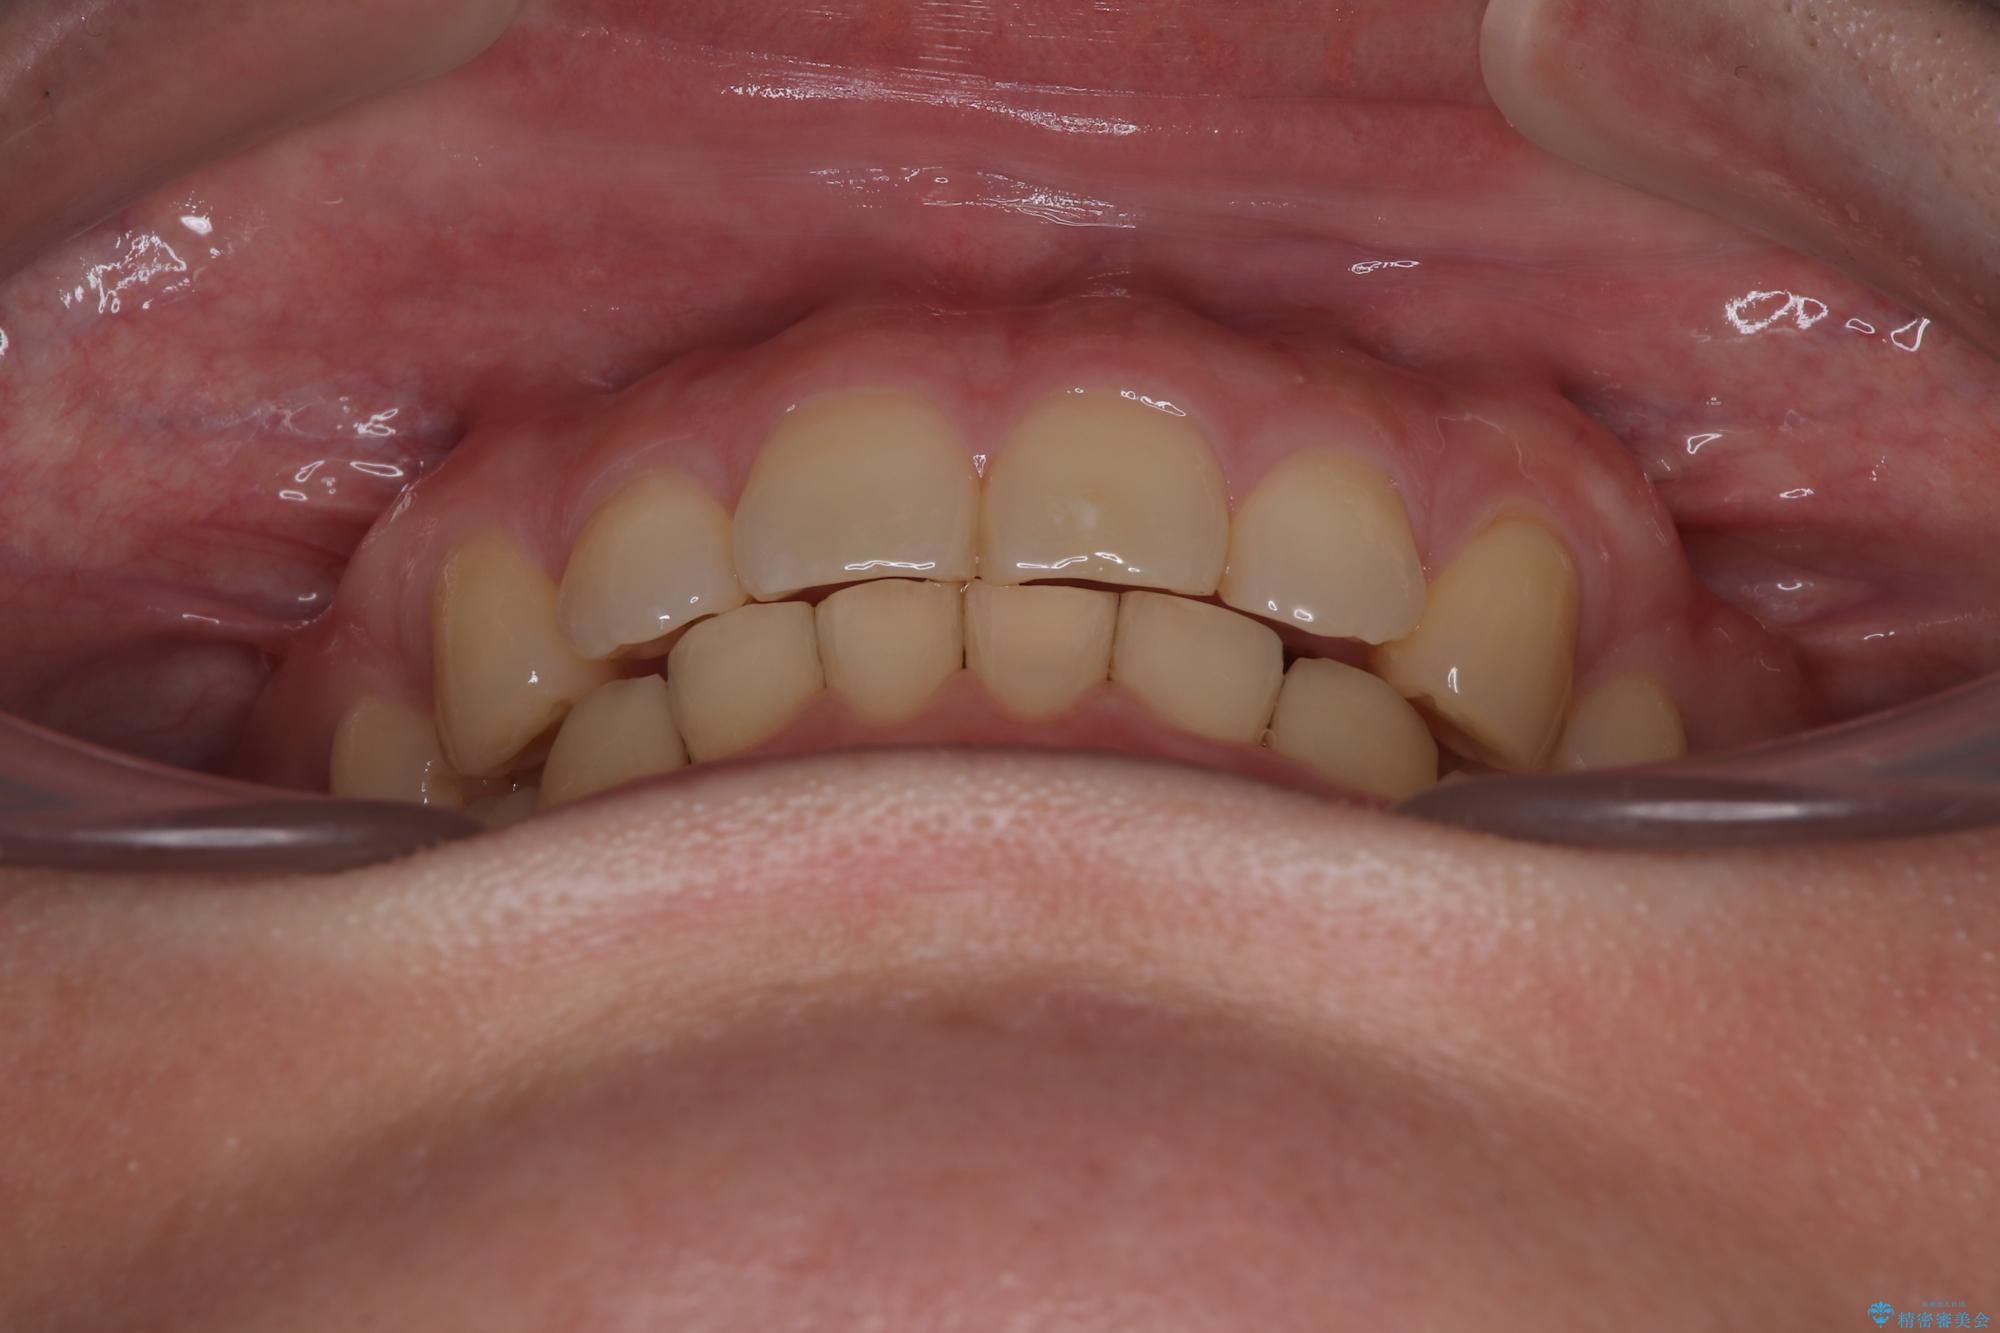

- 下顎前歯が完全に隠れてしまっていることを気にして来院された患者様です。

下顎の臼歯が手前に傾斜していることで咬み合わせが深くなってしまい、下顎前歯が見えないほどに上顎前歯が覆い被さっている状態でした。

咬合力が強いことと、マウスピースを長時間装着する自信がないとのことで、ワイヤー装置にて矯正治療を行うこととしました。

下顎臼歯を起き上がらせるためにユーティリティーアーチを使用し、一気に深い咬み合わせを改善することができました。